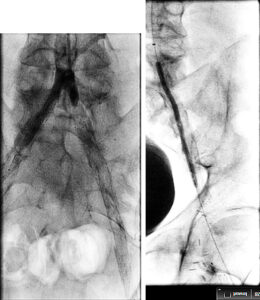

Figure 1. Occluded stent with wire crossing outside the stent

Figure 2. Gradual balloon dilation upsizing from 4-6 mm diameter outside the stent

Figure 3. Angiographic results post stent deployment in the subintimal space.

Access was gained in the left common femoral artery. We advanced a 7-frech Pinnacle 65cm sheath up and over to the right CFA. We were able to probe the vessel outside the previously occluded stent and gain access to the true lumen of the vessel beyond the occluded stent in the distal right SFA. A number of wires were used, including stiff Glidewire and an Amplatz wire. The stiff straight guidewire was used, along with a vertebral catheter, QuickCross catheter, and Trailblazer 0.035 catheter. We dilated the vessels with a 3.5mm Nanocross balloon. We then dilated the right superficial femoral artery with a 6mm balloon, followed by a 7mm balloon. After dilation, right SFA occlusion went from 100% to 60% severe recoil. We deployed 6×120 and 6×80 Supera stents, overlapping them with care to improve stacking of the stents to optimize radial strength. This was in the mid to distal SFA. The completion angiogram revealed a good result, with less than 20% residual stenosis at the SFA post double-barrel stenting. Patient tolerated the procedure well and was kept on DAPT.